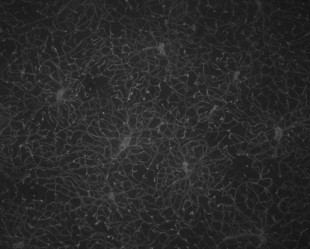

Semantic segmentation of blood vessels is an important task in medical image analysis, but its progress is often hindered by the scarcity of large annotated datasets and the poor generalization of models across different imaging modalities. A key aspect is the tendency of Convolutional Neural Networks (CNNs) to learn texture-based features, which limits their performance when applied to new domains with different visual characteristics. We hypothesize that leveraging geometric priors of vessel shapes, such as their tubular and branching nature, can lead to more robust and data-efficient models. To investigate this, we introduce VessShape, a methodology for generating large-scale 2D synthetic datasets designed to instill a shape bias in segmentation models. VessShape images contain procedurally generated tubular geometries combined with a wide variety of foreground and background textures, encouraging models to learn shape cues rather than textures. We demonstrate that a model pre-trained on VessShape images achieves strong few-shot segmentation performance on two real-world datasets from different domains, requiring only four to ten samples for fine-tuning. Furthermore, the model exhibits notable zero-shot capabilities, effectively segmenting vessels in unseen domains without any target-specific training. Our results indicate that pre-training with a strong shape bias can be an effective strategy to overcome data scarcity and improve model generalization in blood vessel segmentation.